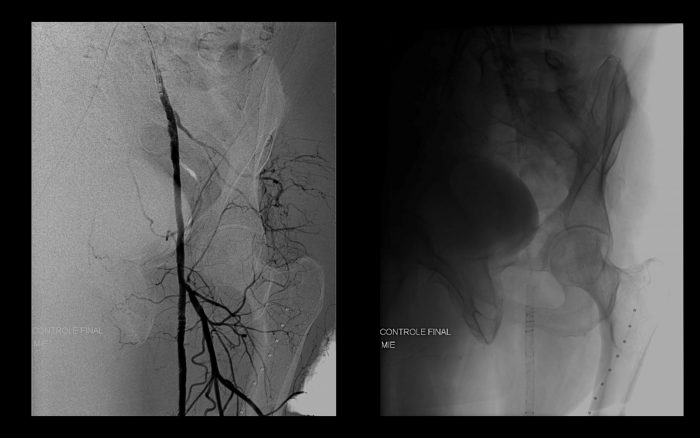

Paciente com história de claudicação dos membros inferiores para curtas distâncias, já submetido a angioplastia do membro inferior direito, retorna ao serviço com piora dos sintomas no lado esquerdo, sem lesão trófica (Rutherford 3)